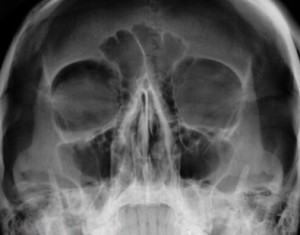

В случае нарушения целостности нижней стенки глазницы, как правило, можно увидеть затемнение гайморовой полости. Оно вызвано кровоизлиянием в нее. Но все же следует учесть, что такое же затемнение может наблюдаться на рентгеновских снимках и при воспалительных процессах в гайморовой полости.

Основой для установления диагноза являются жалобы больного, данные его осмотра, рентгенологическое исследование, КТ и МРТ.

Диагностике «взрывного» перелома нижней стенки глазницы способствуют характерные жалобы больного, среди которых наиболее важной есть двоение при вертикальных движениях глаз. Оно встречающееся у 58 % пациентов.